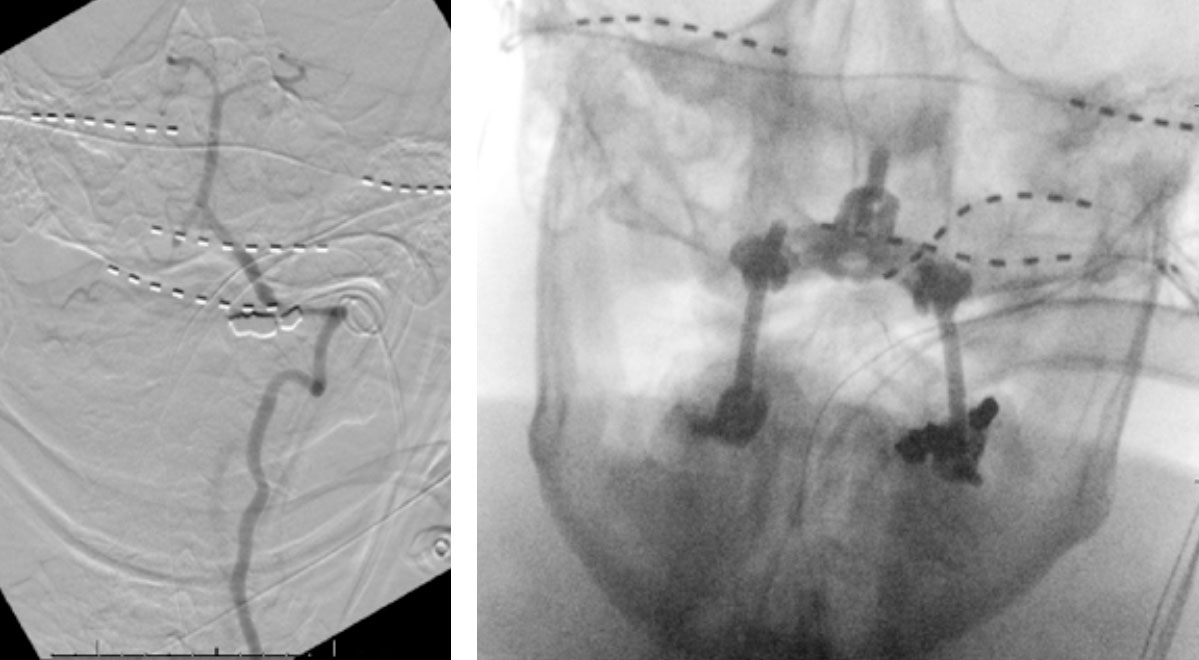

CTA of the neck and brain reveal that the left Vertebral Artery is completely occluded at approximately the C1-C2 level with extensive hypertrophic degenerative osseous changes from C1-C3. Retrograde flow into the post PICA left Vertebral Artery is observed from the co-dominant right Vertebral Artery which appears to be the primary supply into the basilar circulation. No significant Posterior Communicating arteries are observed on either the right or left Carotid Artery on the CTA imaging (Figure 1).

We performed conventional catheter angiography with provocative testing to reproduce his symptoms. The right Vertebral Artery is the codominant primary supply to the basilar circulation with reflux into the distal left Vertebral Artery that is occluded (Figure 3).

During neutral positioning, the vertebrobasilar circulation fills briskly from the Right Vertebral Artery. (Figure 4)

On rotation to the left, the patient experienced mild symptoms, however no significant Vertebral Artery or basilar reduction in flow was observed. On rotation to the right, the patient experiences slightly more moderate symptoms, however no significant Vertebral Artery or vascular reduction flow was observed. On hyper extension of approximately 10-15 degrees, passively performed by the patient until symptoms are reproduced, angiogram demonstrates complete occlusion of the right Vertebral Artery at approximately the C2-C1 level. (Figure 5)